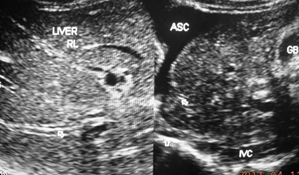

She became HBeAg negative and anti HBe positive in June 2017. HBV DNA was 480 IU/ml on 6’017 and became undetectable by 5’018. The level of transaminases fluctuated mildly from 1.1 to 1.8 X ULN. WBC count was around 2800 to 3100, platelet from 49000 to 95,000 and hemoglobin from 10 to 12 g. As her leukopenia did on improve on filgrastim treatment and WBC count dropped to 1,630/cu mm with 36% neutrophil and platelet count to 43,000/cu mm splenectomy was done on 22.6.018. Presence of micronodular cirrhosis was detected at the operation (Figure 4a). HBV DNA level at this time remained undetectable. Operation was followed by fever and neutrophil leukocytosis of 19,100 with 93% neutrophil and C-reactive protein 78 mg/L and development of ascites within a week. The condition responded to treatment with oral antibiotic and diuretic. During follow-up till February 2020 she remained well with WBC count of about 3400–6200 with hemoglobin around 12g and platelet count that varied from 170,000 to 380,000. In this period she had an episode of fever in September 2018 associated with elevation of CRP to 24 mg but no increase in WBC count. Entecavir controlled the viral replication but had no effect on the levels of transaminases which remained elevated to 1.3 to 2 X ULN. She remained HBsAg positive, HBeAg negative, anti-HBe positive with low HBV DNA 41 IU/ml when last seen in October 2022.

He suddenly developed ascites a month later. Ultrasonography showed ascites with free floating particles indicating presence of bacterial peritonitis, hepatomegaly with uniform increased echo-texture of the liver and prominent hepatic veins with mild splenomegaly. Inferior vena cava showed mild stenosis at the site of hepatic vein opening with thick posterior wall and a large recent thrombus. His blood tests showed WBC 6500/cu mm, neutrophil 70%, platelet 140,000/ cu mm, CRP positive, bilirubin 3.9/1.8mg%, ALT 12.6 X ULN and AP 1.9 X ULN with normal protein and albumin. He refused diagnostic paracentesis. A diagnosis of severe acute exacerbation of HVCS with ascites was made. Jaundice a month back was retrospectively diagnosed as mild acute exacerbation of HVCS. It was supported by mild neutrophil leukocytosis noted at that time. He was treated with oral antibiotic and furosemide. He became free of ascites with ALT 4 X ULN at 1 month and 1.8 X ULN at 3 month. He however, noticed increased pigmentation of the face. The US showed liver with uniform increased echo-texture and endoscopy detected grade I esophageal varices. Possibility of development of cirrhosis was considered. He was hesitant about liver biopsy. As he had gallstone which might act as a focus of infection he agreed for cholecystectomy. At operation the liver was found cirrhotic. Biopsy showed mixed nodular cirrhosis. He remained well with normal ALT. Two years later in July 2009 he developed minimal elevations of ALT 1.8 X ULN followed by recurrence of ascites with dilated superficial veins over abdomen. It responded to treatment with antibiotic and diuretic. He remained HBsAg positive, HBeAg negative, anti-HBe positive and his HBV DNA was 2,410 IU/ml, normal or minimal elevation of ALT elevation during follow up till December 2011 when he migrated to UK to live with his son who is settled there.

At 21 years age this patient suffered from prolonged chronic diarrhea and jaundice. At 39 years he had recurrence of diarrhea, fever, jaundice followed two months later by ascites. A few months later in November 1987 he attended CMC Hospital, Vellore, India where he was detected HBsAg positive, minimal elevation of ALT, mild cytopenia, mild hepatosplenomegaly with increased echo-texture of liver and grade III esophageal varices. A diagnosis of CHB related chronic liver disease was made. In 1989 he had 2 admissions in the same hospital with variceal bleeding and had sclerotherapy. In July 1990 he attended a hospital in Bangkok where splenectomy was done for severe hypersplenism. Presence of micronodular cirrhosis was confirmed at liver biopsy.

Cirrhosis was of micronodular type initially as in case # 2 (Figure 4a) but in patient with recurrent of acute exacerbations it converted to mixed nodular type as in case # 3. Continued prolonged or recurrent acute exacerbations resulted in conversion to macronodular type as was seen in a young boy reported earlier (Figure 4b).41 Thus though the common type of cirrhosis in diseases of HVOO is micronodular in HVCS with recurrent acute exacerbations it eventually evolved into macronodular type.

Figure 4a Micronodular cirrhosis seen during splenectomy for severe hypersplenism in 30 year old CHB patient in replicative phase Case # 2.

Figure 4b Macronodular cirrhosis seen in a young boy with recurrent acute exacerbation of hepatic vena cava syndrome during cholycystectomy for gallstone (reproduced with permission SM Shrestha, S Shrestha . Hepatic vena cava syndrome: a common cause of liver cirrhosis in children in Nepal, Trop Gastroenterol 2014;4:35:85-95).

Figure 4 Liver Cirrhosis in CHB patient with Hepatic Vena Cava Syndrome.